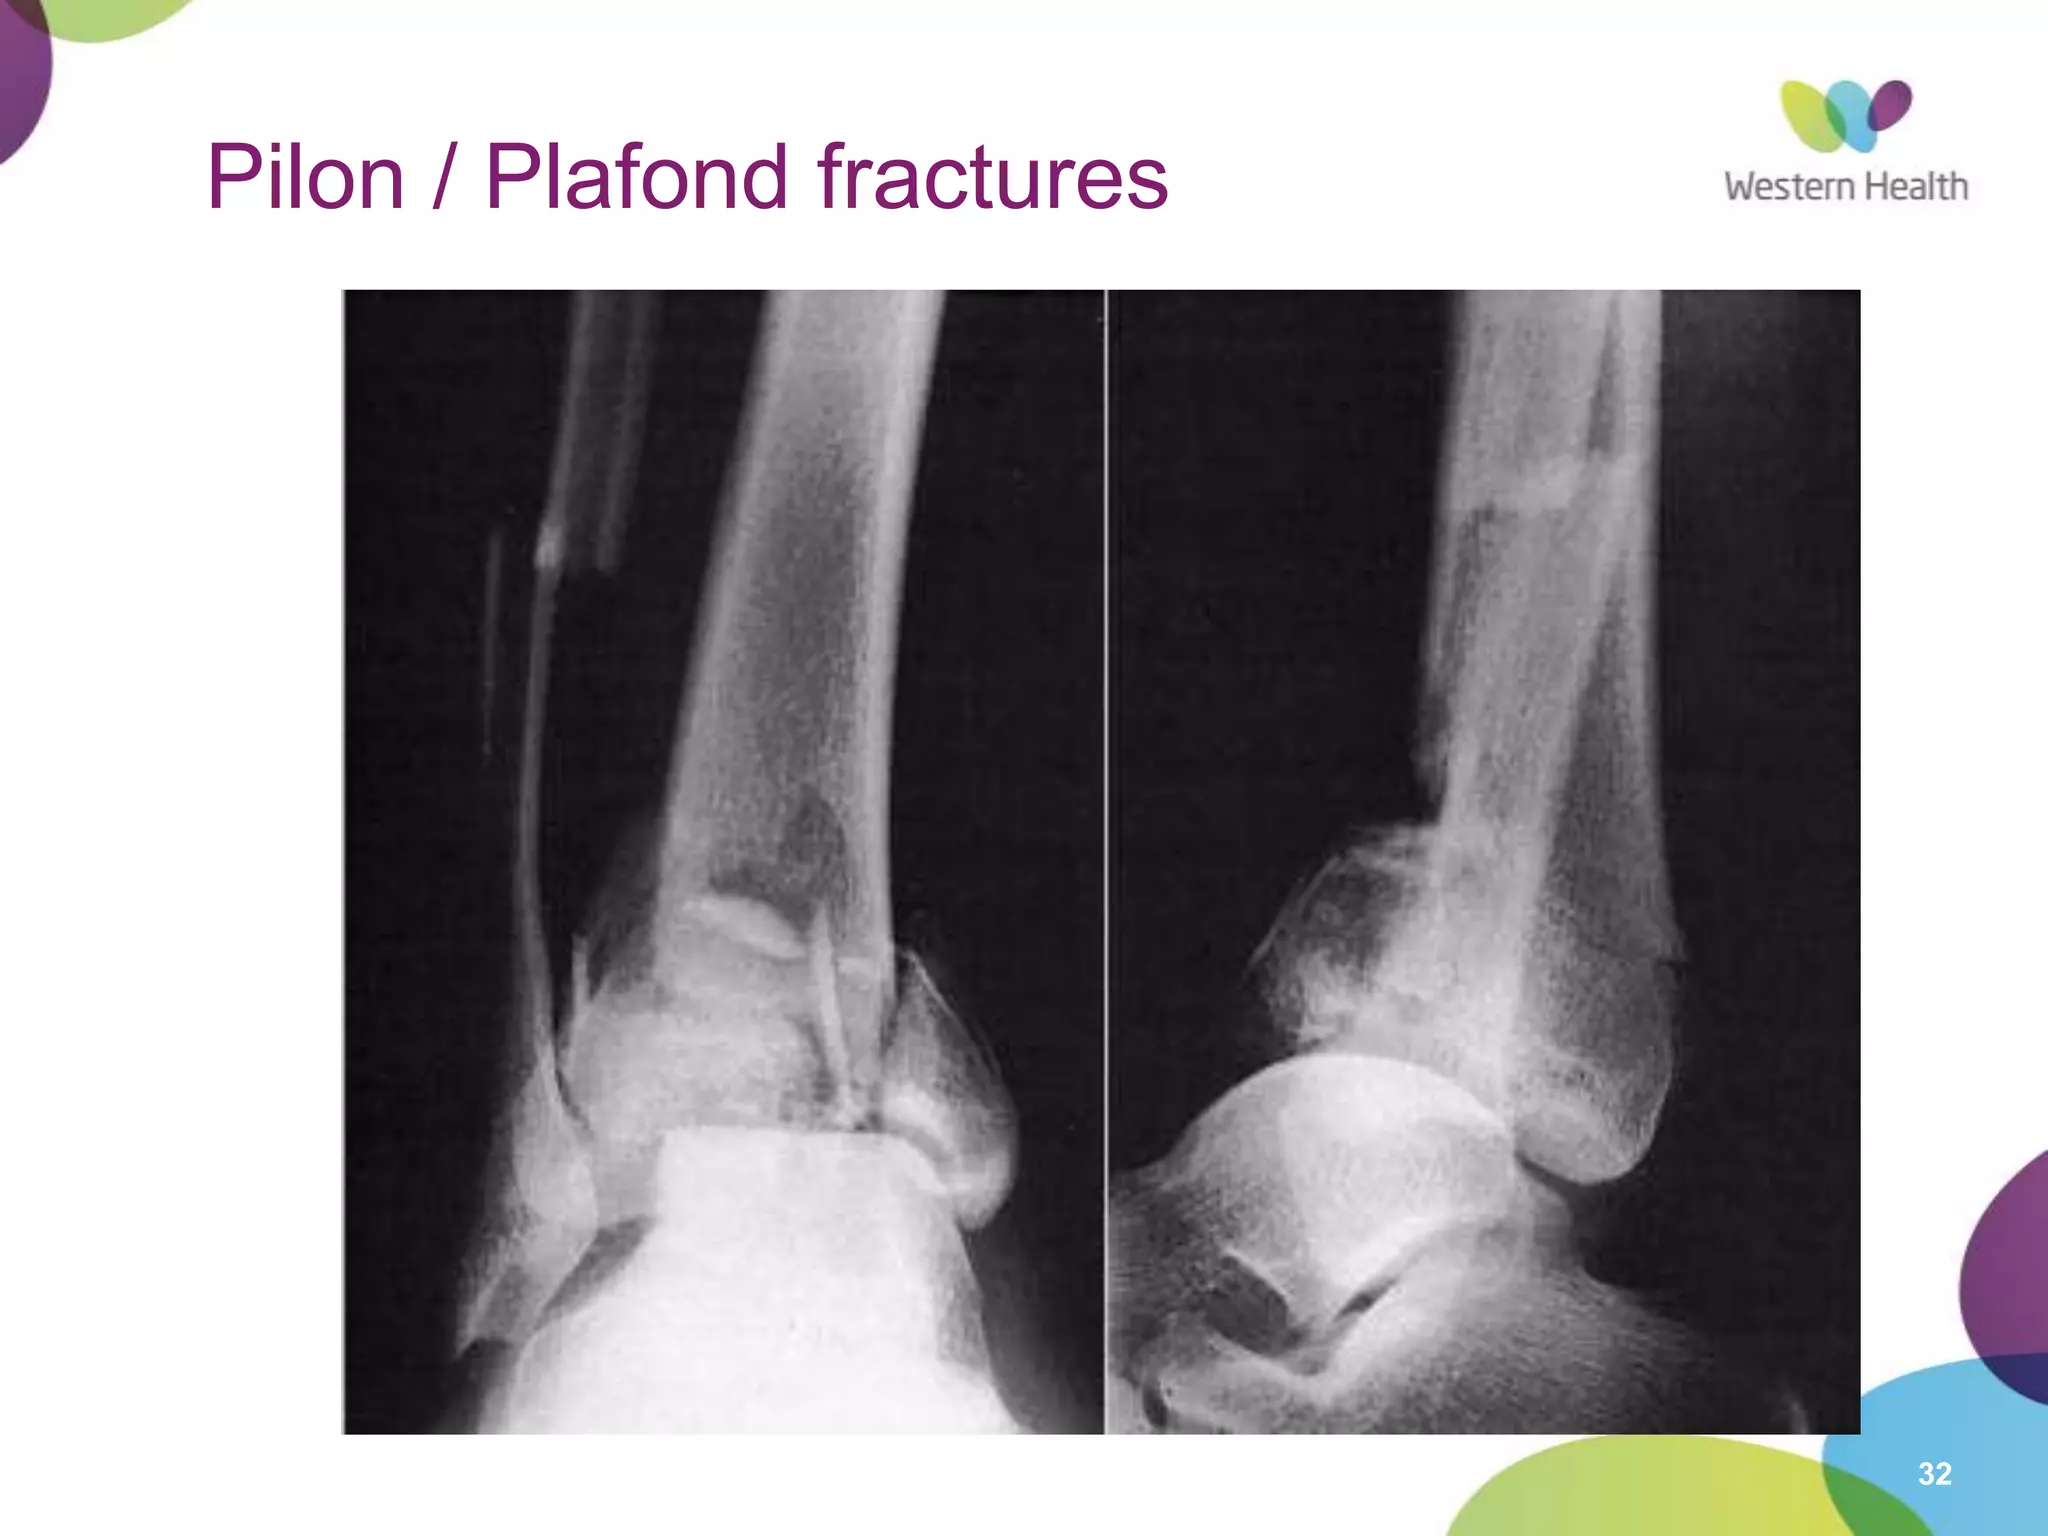

Pilon / Plafond fractures

33

• Fracture of distal tibial metaphysis

– Often comminuted

– Often significant other injuries

• Mechanism

– Axial load

– Position of foot determines injury

• Treatment

– Unstable

– X-ray tib/fib & ankle

– Orthopedic consultation